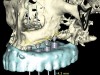

Three types of computer-generated surgical guides are available: tooth-supported, mucosa-supported, and bone-supported. Tooth-supported guides are used in partially edentulous patients; the guide rests on teeth in the arch for accurate fit. Mucosa-supported guides rest on mucosa and are primarily used in completely edentulous patients. Accurate inter-arch bite registrations are important when using these guides to assure precise guide positioning and placement of securing screws or pins prior to implant placement (Figure 1). Bone-supported guides can be used in partially or completely edentulous patients, with their primary use being in completely edentulous applications when ridge atrophy is present and good seating of a mucosa-supported guide is questionable. An extensive full-thickness flap is necessary when using bone-supported guides to expose the bone in the implant sites and adjacent areas for an intimate fit of the guide over the bony ridge.